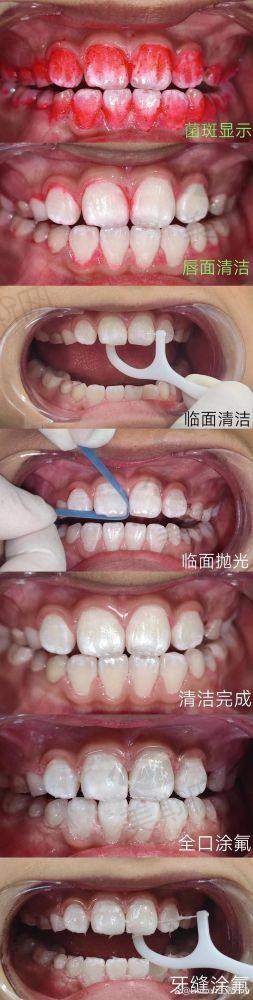

口腔儿童齿科价格表

全口涂氟 | 8元起 |

树脂窝沟封闭单颗 | 6元起 |

儿童玻璃补牙修补蛀牙 | 50元起 |

乳牙拔除 | 9.9元起 |